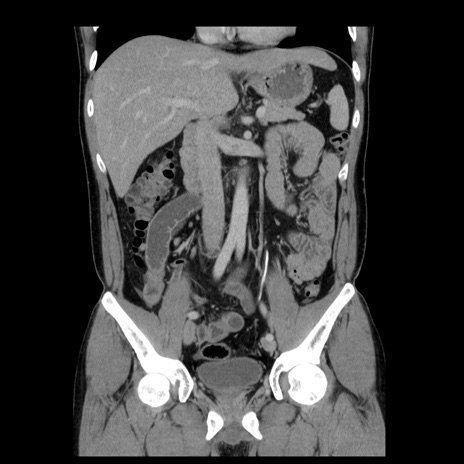

症例4(冠状断像)

【症例】30歳代男性

【主訴】腹痛、嘔吐

【現病歴】昨晩から突然の腹痛あり、その後嘔吐、軟便も出現。腹痛が改善しないため救急搬送となる。2日前にしめ鯖の食事歴あり。

【身体所見】意識清明、苦悶様、BP 135/90mmHg、BT 35.7℃、腹部:平坦、やや硬、心窩部〜臍部に自発痛、圧痛あり、筋性防御+、反跳痛-

【データ】WBC 8100、CRP 0.57